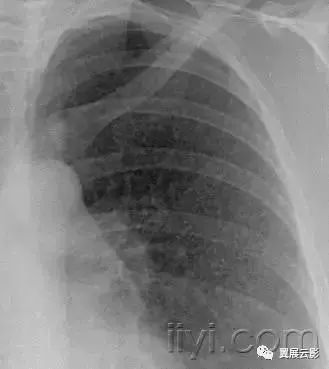

十九、肺实变:

平片和CT:肺实变表现为肺实质密度的均匀一致性增高,导致肺血管和气道壁边缘不清。有时可见含气支气管征。只有在极少数的情况下,肺实变的密度变化有助于鉴别诊断,例如脂性肺炎是密度减低,胺碘酮中毒时密度增高。

图示为多灶性的肺实变。